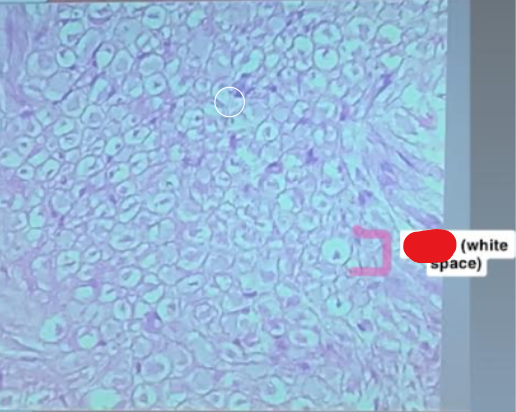

Label The White Space

Myelin

Label the LAYER around the axon

Endoneurium